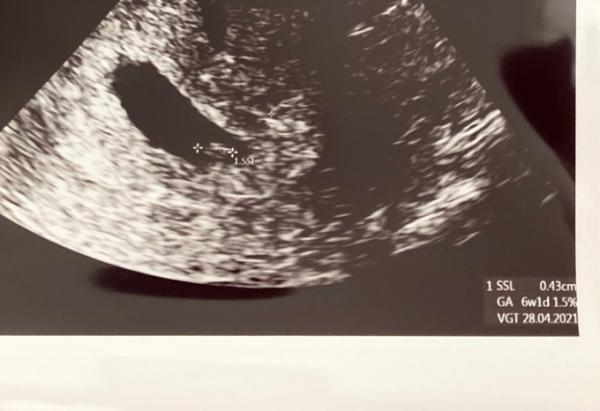

Hallo ihr Lieben! Nachdem ich ja gestern ja eine leichte braune Schmierblutung hatte durfte ich bereits heute bei 6+2 zum Arzt und was soll ich sagen: man konnte tatsächlich schon den kleinen Embryo mit 0,43cm sehen und das kleine Herzchen hat auch schon geschlagen! Meine Ärztin meine es ist eher 6+1 anstatt 6+2, aber genaueres kann sie vermutlich beim nächsten Termin sagen. Da bekomme ich dann auch den Mutterpass mit, sobald auch alle Laborwerte da sind. Bin gerade überglücklich und kann es noch gar nicht glauben.

Bild zu 1. FA-Termin ✅ - Forum für April - Mamis